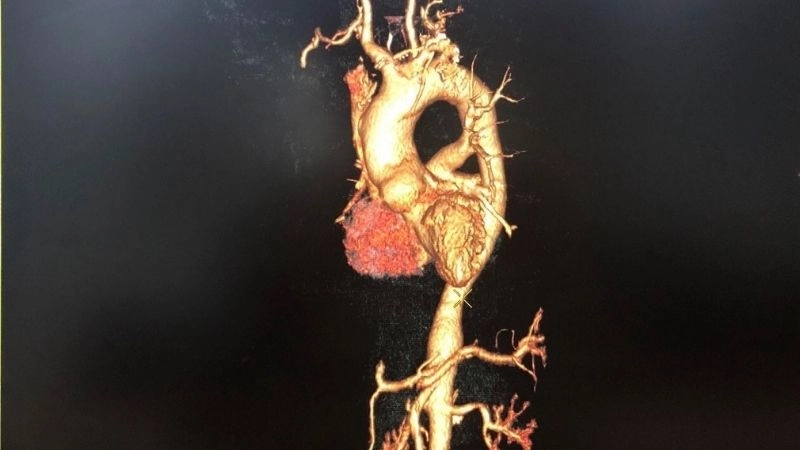

Takayasu's arteritis diagnosis with imaging tests

Images visual examples of Takayasu's arteritis

Takayasu's arteritis is a rare chronic inflammatory disease affecting large blood vessels, particularly the aorta and its branches, leading to narrowing and reduced blood flow.